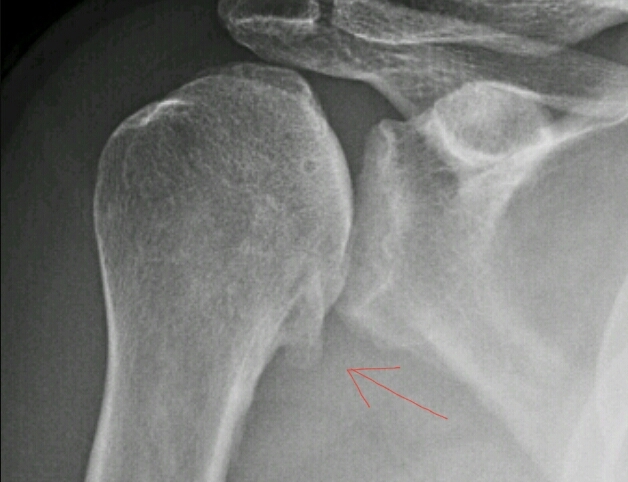

Name the feature the red arrow is pointing at. What disease does this correlate with?

osteophyte at glenohumeral joint

previous trauma or underlying CPPD